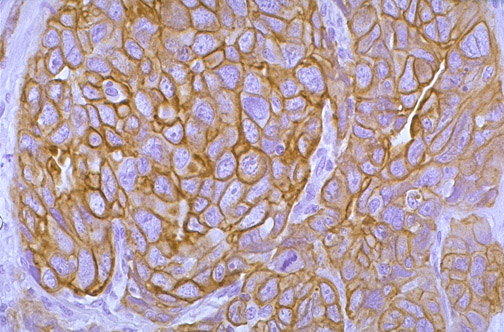

CK-7 is a cytokeratin found in carcinomas. Immunoperoxidase staining with various cytokeratins is useful for distinguishing different types of carcinomas. Seen here is CK-7 staining of an ovarian carcinoma.